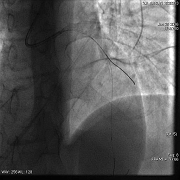

◆冠脉造影结果

◆左主干未见斑块及狭窄,前降支近段可见斑块,狭窄约50-60%,中段分出第二对角支后完全闭塞,血流Timi0级,回旋支中段及远段斑块,狭窄约80-90%,血流Timi3级,右冠全程管壁不规则,斑块狭窄约30-40%。

冠脉造影(左冠)

罪犯血管:左前降支